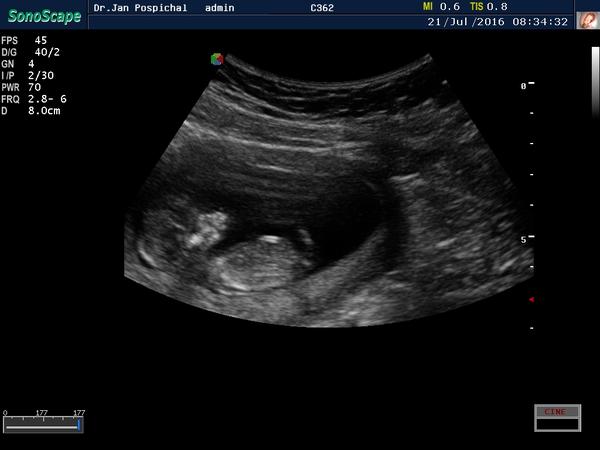

Je to holčička nebo chlapeček? Foto ultrazvuku

Ahoj maminky a budoucí maminky 😉 Prosím, poradila byste mi některá, co vidíte na fotce z ultrazvuku ve 20. týdnu za pohlaví? Určitě jste foteček viděly už mraky, proto vás žádám o radu...Nechci nikoho ovlivnit, proto svůj tip řeknu později 🙂 Děkuju moc!!!

@matylda123 kavove zrno tam neni. Bych ti to zakrouzkovala,ale z mobilu to nejde. Muj tata takhle na utz poznal diky mocove trubici nasi treti dcerku v 16 tt,primo v primem prenosu mi ukazal mocovou trubici a jak zrovnw cura a ta trubice byla rovne a koncila spolu s telem. Tady jde sikmo nahoru a jeste vystupuje z tela. Aspon jsem to vyfotila bliz. Tak jsem zvedava 🙂 pri dalsim utz nspis. A fotku zespoda nemas?

@matylda123 tak jeste super vyrez,co presne myslim 🙂

@estrellita moc díky za info 🙂 ne jinou fotku nemám... V úterý dám vědět, ale taky si myslím, že to vypadá na pinďoura 🙂

@estrellita ještě mě napadlo že to je vyfoceny rychlý pohyb ruky dolů...No v úterý se to dozvíme 🙂

@matylda123 ruka vede niz,sleduj kost od raminka,ta je hezky videt.

Je to kluk holky 🙂

Hlásím,že máme potvrzeného Vojtíška a je to prý pořádný bobíšek 🙂 hlavně,že se má v bříšku dobře 🙂

@matylda123 tak opravdu jsem videla mocovou trubici,tata mi to vcera potvrdil,ze ano,ze to tak vypada,ale on neni gyn,tak rekl,ze kdyz ten utz nevidi v realnem case,ze samozrejme jiste to ruct nemuze. Tak mu to reknu 🙂

@matylda123 ale jinak krasna fotka